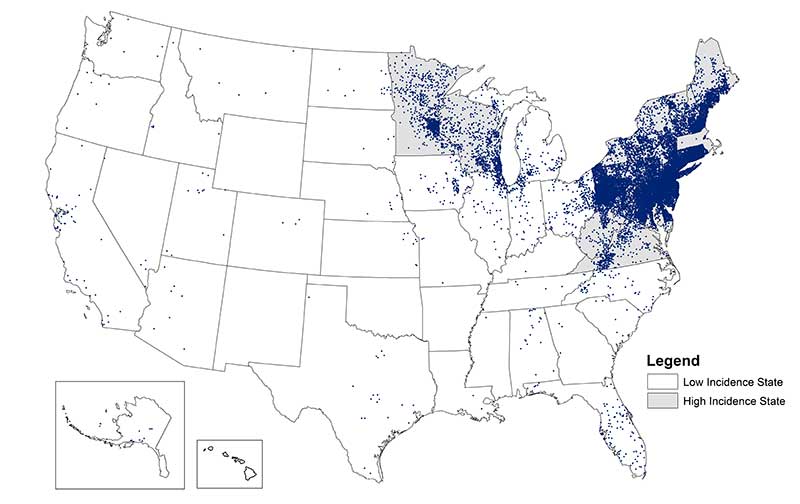

This disease caused by a spirochete, is the most common tick-borne infection in the United States

What is Lyme Disease?

While many cases are asymptomatic, this tick-borne illness can cause a malaria-like syndrome with hemolytic anemia

What is Babesiosis?

These bacteria are spread to people primarily through the bite of infected ticks including the lone star tick. On test questions, it tends to occur in the Ozarks region between AR and MO. Geographical distribution is shown below:

What is Ehrlichia?

(E. chaffeensis, E. ewingii, or E. muris eauclairensis)